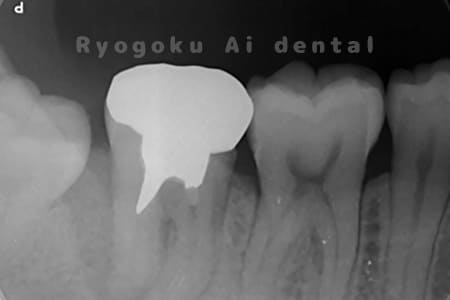

他院で虫歯が大きく、抜歯と判断され、インプラント手術を提案された患者様です。親知らずが残存していたため、自家歯牙移植手術を行いました。

<リスク・副作用>

治療後、痛みや違和感、出血、腫れなどが出る事があります。喫煙者、糖尿病などの方の場合、歯が生着しない場合があります。